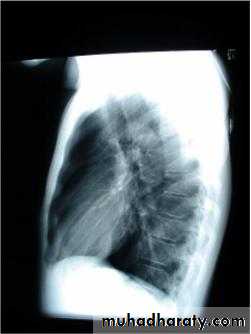

Investigations :-

1-Chest X-Ray2-CT chest